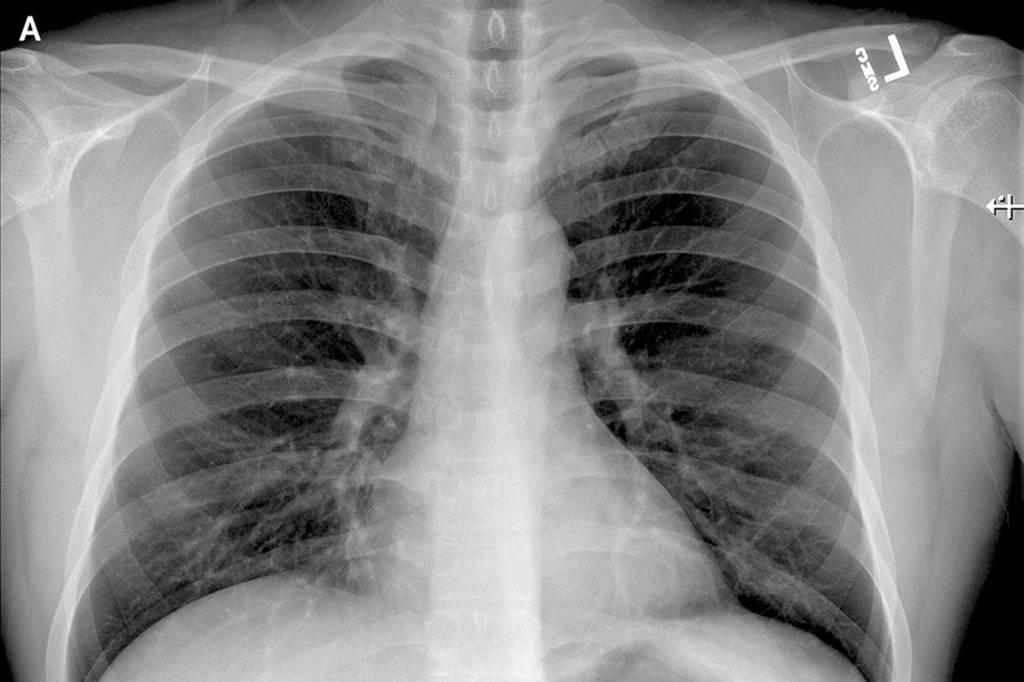

Posteroanterior and Lateral Chest Radiographs, January 19, 2020 (Illness Day 4).No thoracic abnormalities were noted (Snohomish Health District)